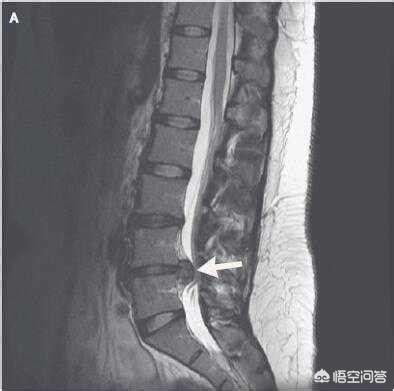

症状は腰痛と下肢痛の典型的な症状で、しびれ(電球がチカチカする)を伴い、神経の異常放電があり、当時はまだ医学の勉強をしていなかったので、町立病院の自宅でMRIを撮ったところ、黒いフィルムが送られてきた。......